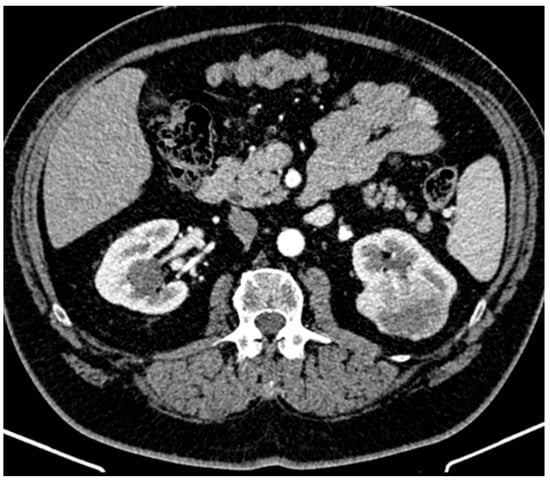

The patient did not meet the criteria for rheumatoid arthritis based on the 2010 ACR/EULAR Rheumatoid Arthritis Classification Criteria given the negative serology for rheumatoid factor and cyclic citrullinated peptide. Other autoimmune diseases were excluded as well. The presence of systemic symptoms (fever and chills), mild leukocytosis, and elevated inflammatory markers in a diabetic with an ICD was highly suggestive of IE and the patient was transferred to the cardiology department of another hospital for further evaluation. The diagnosis of IDCM was confirmed, but the transthoracic (TTE) and transesophageal (TOE) echocardiography did not reveal vegetations. Three separately collected blood samples of 10 mL each were obtained within 24 h, prior to antibiotic initiation, during fever episodes, following strict aseptic and antiseptic protocols. Subsequently, daily blood samples of 10 mL were collected during fever episodes, with antimicrobial-neutralizing agents. All blood cultures were monitored for up to three weeks. Due to the persistence of infectious symptoms, empirical antibiotic therapy was started. To identify a potential infectious collection, a thoracic and abdominal computed tomography (CT) was performed, revealing a mass at the upper pole of the left kidney suggestive for a renal tumor (Figure 1). The patient was referred to the urology department of our hospital. The abdominal magnetic resonance imaging (MRI) confirmed a renal tumor of 6.3 cm diameter, with contrast enhancement and the presence of a “washing out” phenomena.

Figure 1. Abdominal computed tomography revealed a left kidney mass extending into the perirenal fat up to the renal fascia without invading it, involving the upper calyceal groups.